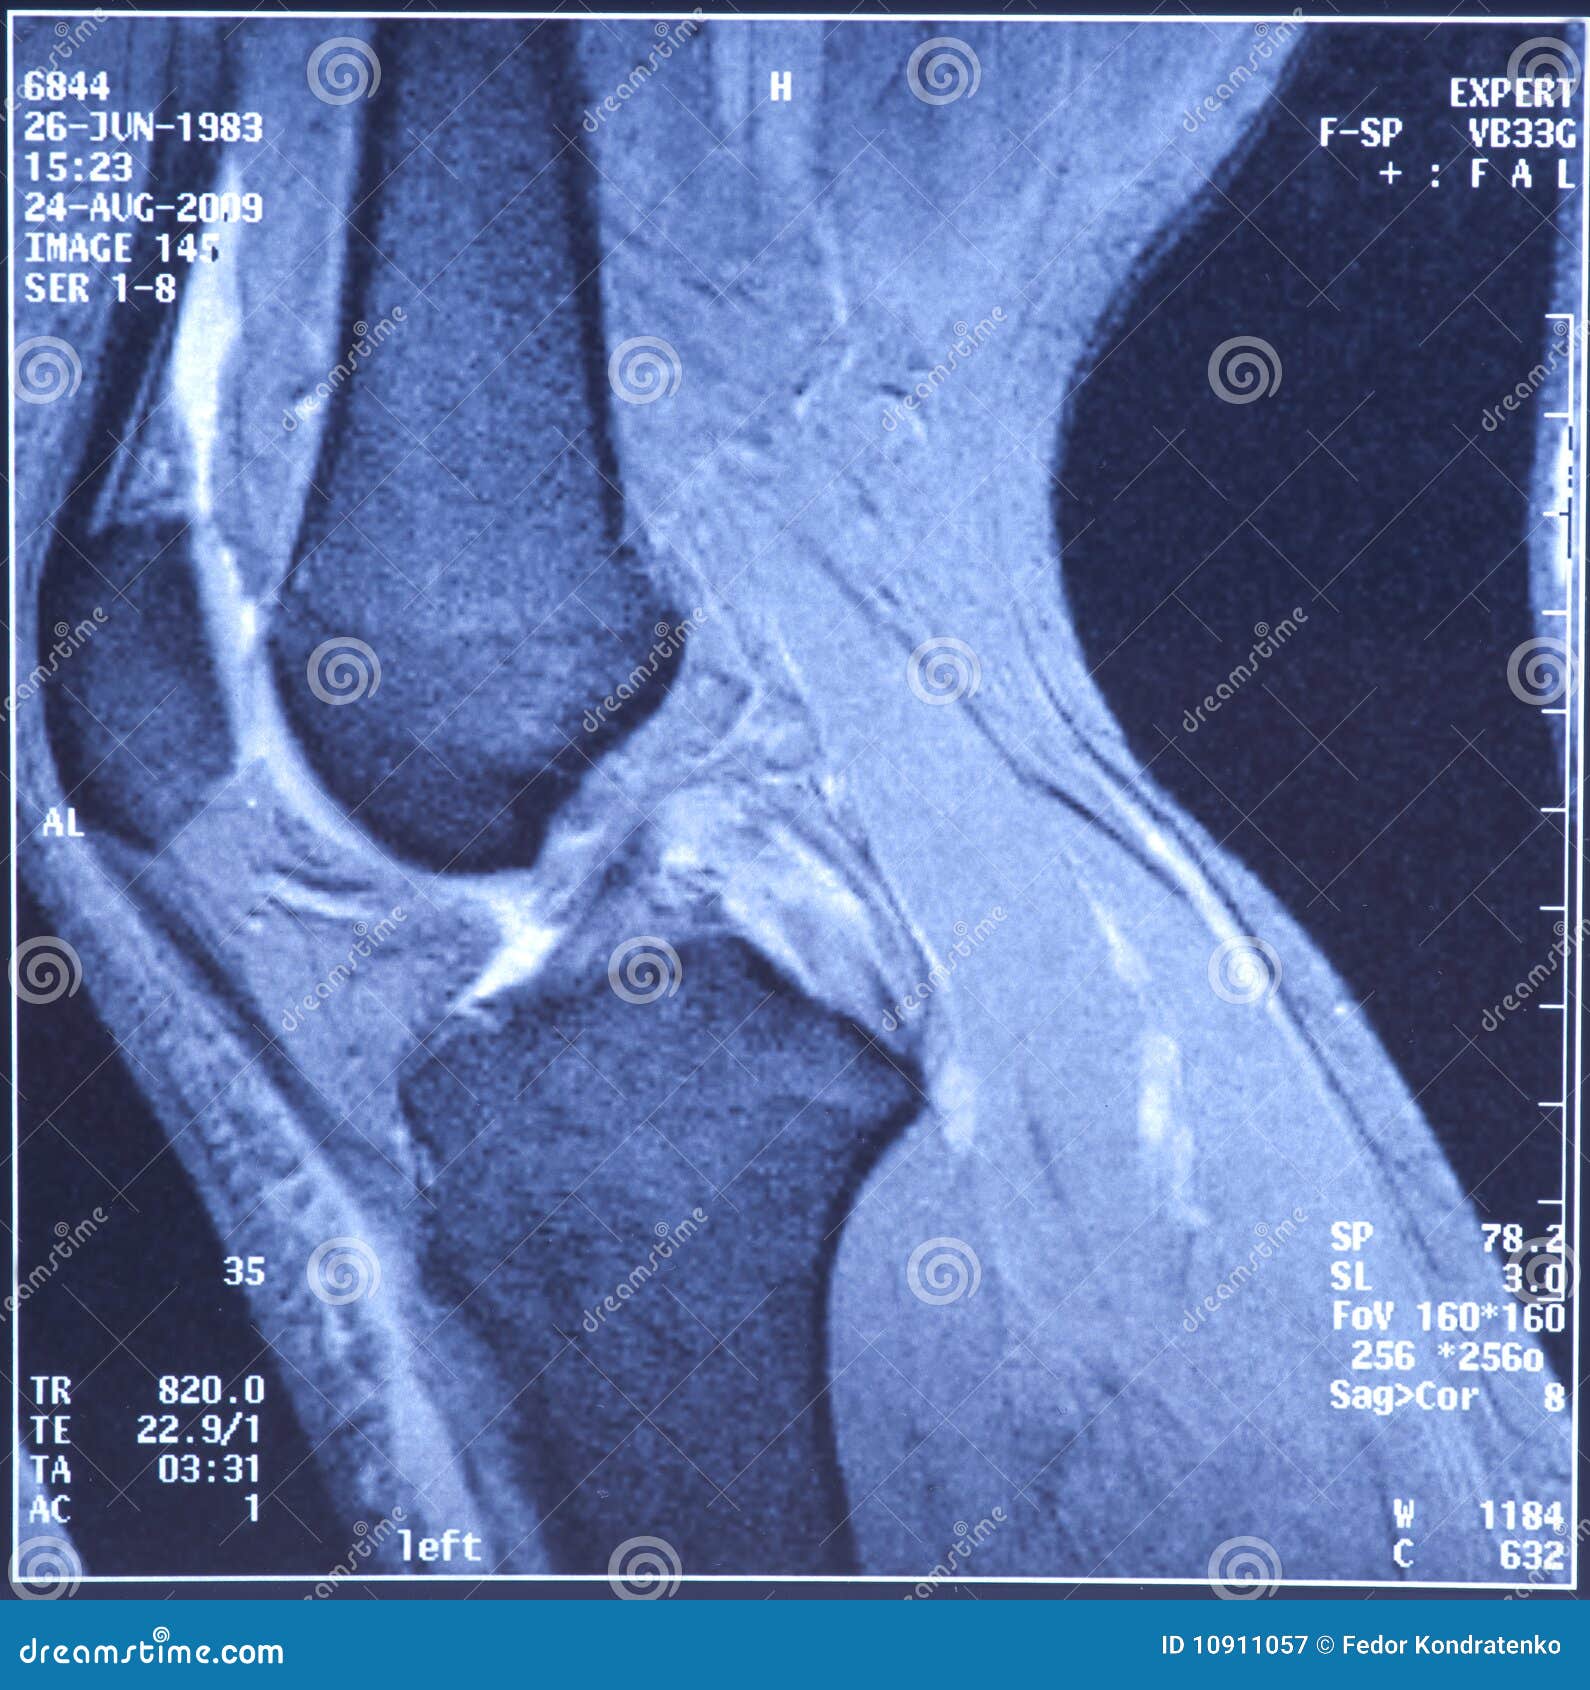

My Knee MRI Damage of Crossshaped Ligaments Stock Image Image of Dashboard Injury Knee Mri Mri allows reliable assessment of knee ligament structures and therefore is the image modality of choice in diagnosing knee ligament instability. Mri findings can reveal the traumatic mechanisms in many acute knee injuries. Diagnosis can be suspected clinically with a traumatic knee effusion and increased laxity on a posterior drawer test but requires an mri for confirmation. Five classic bone. Dashboard Injury Knee Mri.

Dashboard Injury Knee Mri . Bone contusions with or without fractures are a common mri finding seen in traumatic knee injuries. Five classic bone contusion patterns have been described: Mri findings can reveal the traumatic mechanisms in many acute knee injuries. Diagnosis can be suspected clinically with a traumatic knee effusion and increased laxity on a posterior drawer test but requires an mri for confirmation. When indicated, radiographs are the mainstay of the initial imaging for suspected knee injury. Mri allows reliable assessment of knee ligament structures and therefore is the image modality of choice in diagnosing knee ligament instability. It can act as an indicator towards the mechanism of injury. Pattern of bone contusion in knee injuries can give clues for the mechanism and associated injuries. Knee injury patients with a high clinical. This review presents these five injuries, emphasizing relevant anatomy, normal mri appearances, common injury patterns, and tips to avoid overlooking them. By applying a biomechanical approach in mri interpretation, it is possible to use easily.